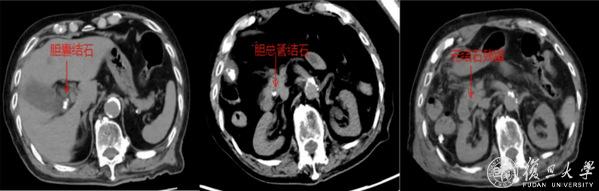

近日,100岁的陈爷爷突然右上腹剧痛、高烧不退,急诊确诊为:胆囊结石伴急性胆囊炎、胆总管结石伴急性胆管炎。老人免疫力差,感染像野火一样蔓延,再不动手术就可能休克甚至丧命,但传统开腹手术创伤大,术后并发症风险极高,对百岁老人来说更是风险堪比“走钢丝”,如何选择手术方式成为治疗关键。

经多学科团队综合评估后,复旦大学附属浦东医院肝胆外科主任王晓亮、主任医师李春生团队决定采用腹腔镜联合经胆囊管胆总管取石术(TC-CBDE)帮助老人渡过难关。

手术台上,医生先切除了穿孔坏疽的胆囊,再像“穿针引线”一样,通过胆囊管这个“天然隧道”,把胆总管里的结石一颗颗取出来。全程90分钟,未出现胆道损伤、出血等并发症。术后重症医学科蔡金芳主任团队监护治疗,为老人安全保驾护航。术后第二天转入普通病房,术后7日便康复出院。